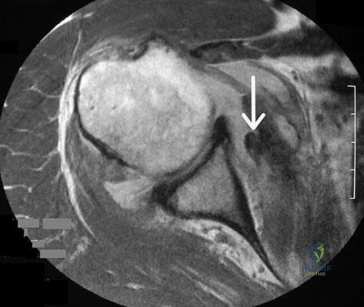

A 28-year-old volleyball player presents with insidious onset of shoulder pain and weakness.

Examination reveals weakness in external rotation but normal strength in abduction. Entrapment of the suprascapular nerve is suspected. At what anatomical site is the compression most likely occurring?

A 24-year-old athlete sustains recurrent anterior shoulder dislocations. An MRI reveals a Hill-Sachs lesion. Advanced imaging and 3D modeling demonstrate that the lesion 'engages' the anterior glenoid rim when the arm is in abduction and external rotation. According to the glenoid track concept, how is this lesion classified?

Explanation